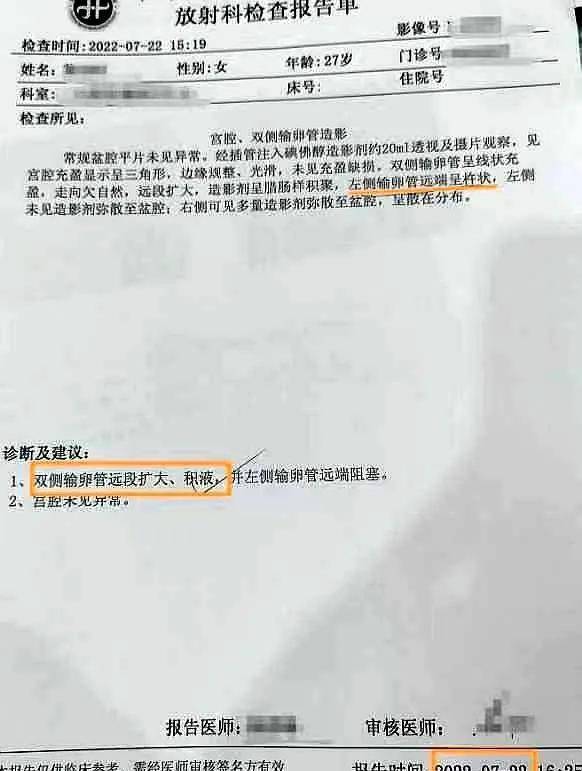

女科医话 - 庞震苗教授中药治疗输卵管积液型不孕一例_mm_卵巢_诊断

图片尺寸582x771